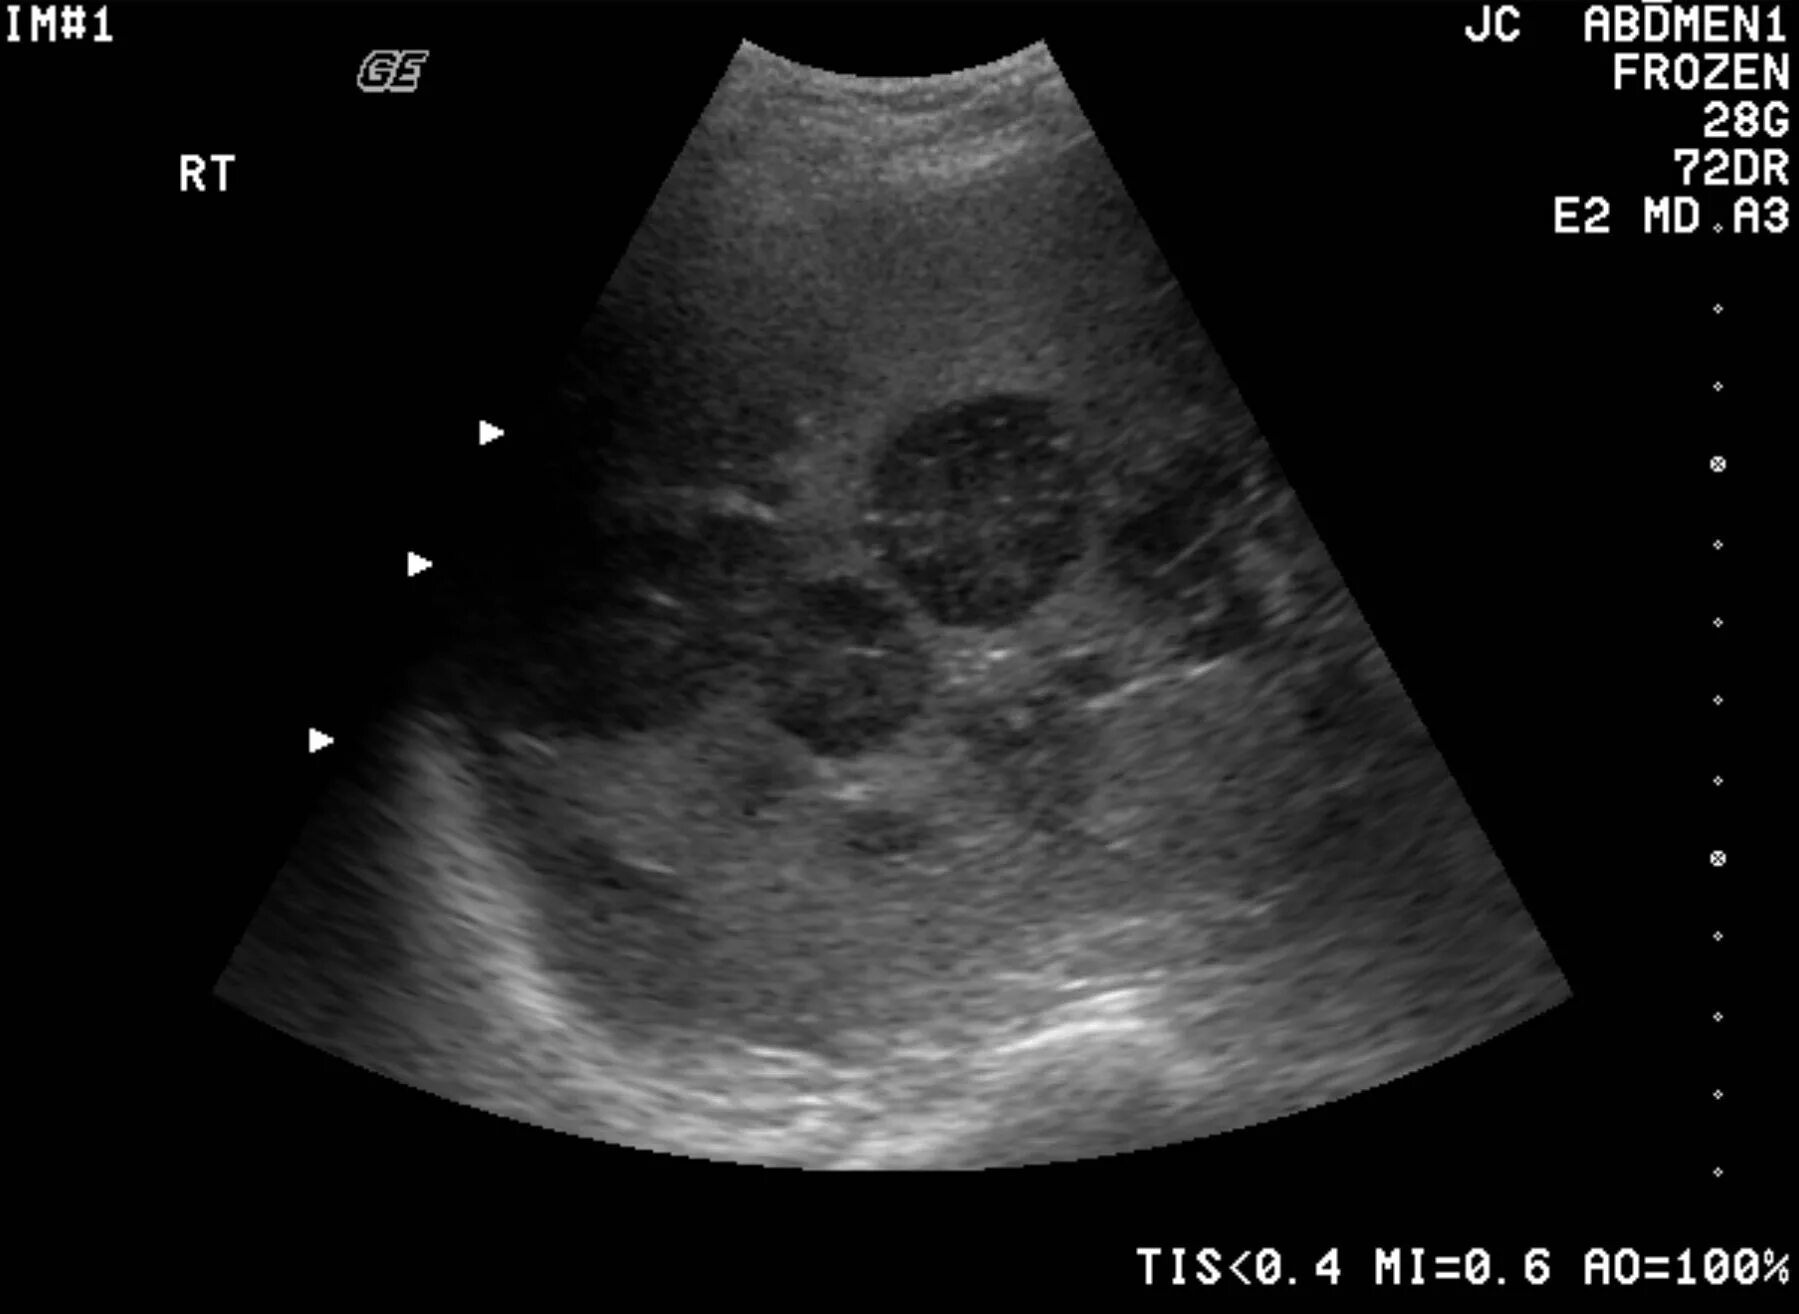

Метастазы в печени на узи